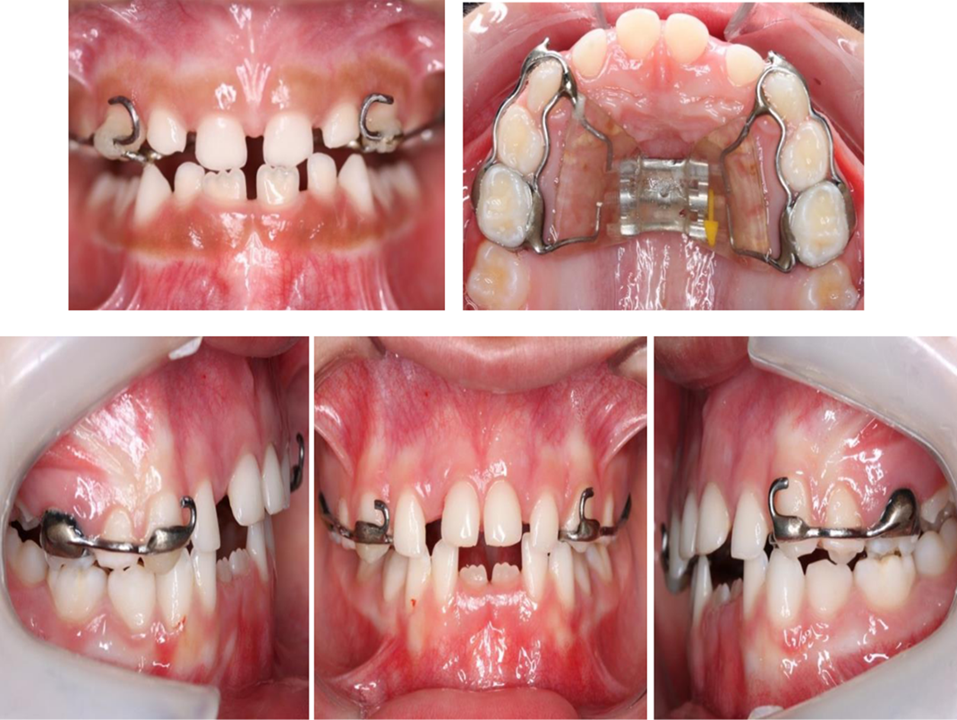

Autor: María Gabriela Flores Bracho. Fuente: Historia Clínica de M. C. M. H. 6 años. 04- 2010. Paciente con aparato encapsulado cementado en boca, fijado con acrílico en el sector del tornillo para inmovilizarlo después de la expansión rápida. Se observa diastemas en zona central que nos muestra la separación de la sutura media pos ERM y mejora en la relación de overjet.

Figura 7. Fotos intrabucales. Pos-expansión rápida de la maxila con aparato tipo Hass modificado.

Autor: María Gabriela Flores Bracho. Fuente: Historia Clínica de M. C. M. H. - 7 años, 09-2011